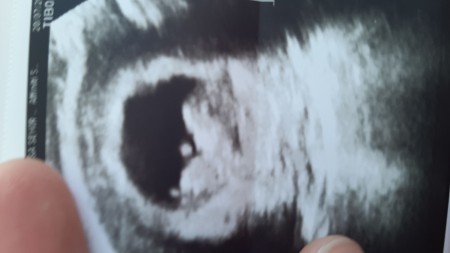

Kizlar sence bellimi

Gebelik haftası 11+6

Kızlar bu da benim bebişim16 hafta sizce kızmı erkek mi

Cinsiyet gözükmüyor ki orda, bebeğin yandan fotoğrafı bu